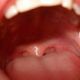

El locutor del sorteo del Loto Plus no pudo terminar su trabajo porque se le secó la garganta: quedaron los micrófonos abiertos. La jugada del Loto...